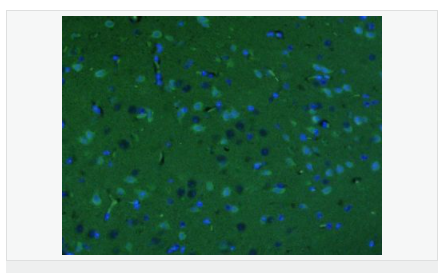

| 產(chǎn)品應(yīng)用 | ELISA=1:5000-10000 IHC-P=1:100-500 IHC-F=1:100-500 IF=1:200-800 (石蠟切片需做抗原修復(fù)) not yet tested in other applications. optimal dilutions/concentrations should be determined by the end user. |

| 產(chǎn)品介紹 | This gene encodes a member of the corticotropin-releasing factor family. The encoded preproprotein is proteolytically processed to generate the mature neuropeptide hormone. In response to stress, this hormone is secreted by the paraventricular nucleus (PVN) of the hypothalamus, binds to corticotropin releasing hormone receptors and stimulates the release of adrenocorticotropic hormone from the pituitary gland. Marked reduction in this protein has been observed in association with Alzheimer's disease. Autosomal recessive hypothalamic corticotropin deficiency has multiple and potentially fatal metabolic consequences including hypoglycemia and hepatitis. In addition to production in the hypothalamus, this protein is also synthesized in peripheral tissues, such as T lymphocytes, and is highly expressed in the placenta. In the placenta it is a marker that determines the length of gestation and the timing of parturition and delivery. A rapid increase in circulating levels of the hormone occurs at the onset of parturition, suggesting that, in addition to its metabolic functions, this protein may act as a trigger for parturition. [provided by RefSeq, Nov 2015] Function: This hormone from hypothalamus regulates the release of corticotropin from pituitary gland. Subunit: Interacts (via C-terminus) with CRFR1 (via N-terminal extracellular domain). Subcellular Location: Secreted. Similarity: Belongs to the sauvagine/corticotropin-releasing factor/urotensin I family. SWISS: P06850 Gene ID: 1392 Database links: Entrez Gene: 1392 Human Entrez Gene: 12918 Mouse Omim: 122560 Human SwissProt: P06850 Human SwissProt: Q8CIT0 Mouse Unigene: 75294 Human Unigene: 290689 Mouse Unigene: 10349 Rat Important Note: This product as supplied is intended for research use only, not for use in human, therapeutic or diagnostic applications. CRF陽性神經(jīng)元的胞體廣泛分布于下丘腦的室旁核、背縫核和藍(lán)斑核,這些區(qū)域也是去甲腎上腺素(NE)神經(jīng)元與5-羥色胺(5-HT)神經(jīng)元密集的區(qū)域。 CRF既具有神經(jīng)遞質(zhì)的性質(zhì)又具有神經(jīng)激素的性質(zhì)。CRF是聯(lián)系神經(jīng)系統(tǒng)與內(nèi)分泌系統(tǒng)的橋梁,在情感障礙疾患如焦慮和抑郁的發(fā)病中發(fā)揮重要作用. |